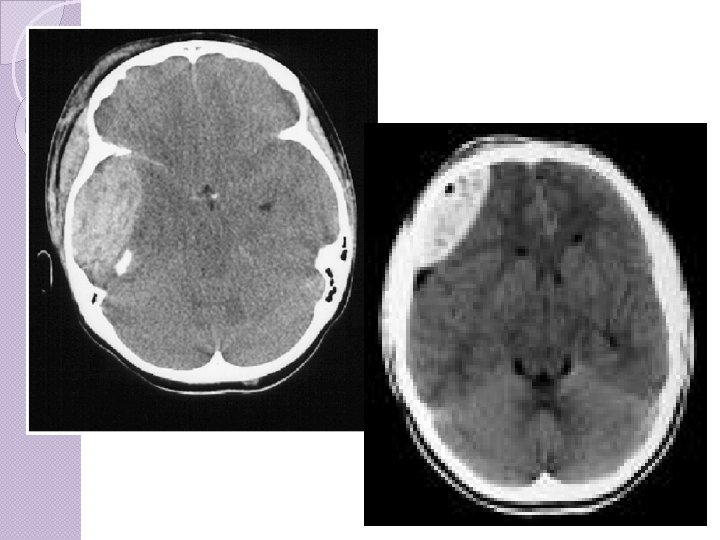

CLASSIFICAÇÃO Hematoma ◦ ◦ ◦ ◦ subdural: Mais freqüente que hematoma epidural Veia entre o córtex cerebral e o seio venoso. Recobrem toda a superfície do hemisfério. Comprometimento cerebral mais grave Prognóstico mais reservado que epidural Tto precoce, se sintomático Atraso maior que 4 hs: Mortalidade 59 69%;

Hematoma subdural A velocidade de formação do hematoma é variável de horas a dias. Inicialmente o sangue se coagula, mas vai lentamente se fluidificando por ação de fibrinolisinas. Os hematomas subdurais agudos podem causar hipertensão intracraniana elevada e hérnias. Além do tipo agudo, os hematomas subdurais podem ser crônicos, isto é, desenvolver-se lentamente, ao longo de semanas, após traumas pequenos esquecidos pelo paciente e desconhecidos familiares. São comuns em idosos e podem ser bilaterais

Hematoma subdural O quadro clínico é de deterioração gradual das funções mentais e da consciência, chegando ao coma, devido à compressão cerebral. Hematomas subdurais também podem ocorrer na infância por trauma obstétrico ou quedas.

Hematoma subdural